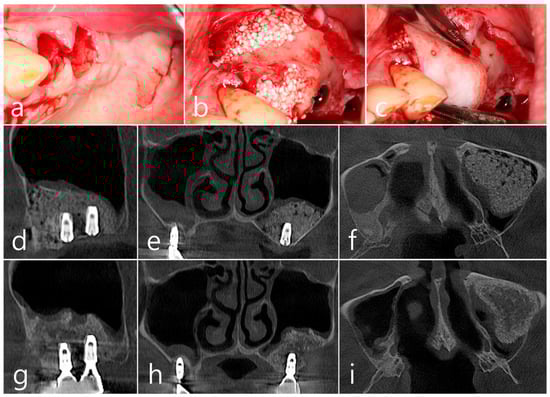

Under local anesthesia, teeth #24 and #25 were extracted, midcrestal and vertical incisions were performed, and mucoperiosteal flaps were reflected (Figure 8a). A lateral sinus window was prepared in the buccal sinus wall, and sinus floor elevation was performed without membrane perforation. As a bone graft substitute, 1 cc of Osteon II (Genoss, Suwon, Republic of Korea) hydrated with saline solution was used (Figure 8b), and a resorbable collagen membrane (Genoss, Suwon, Republic of Korea) was covered (Figure 8c). The flap was closed using 4-0 nylon. Healing was uneventful, and there were no clinical symptoms until 6 months after surgery.

In the CBCT image taken immediately after the procedure, a well-filled bone graft substitute without perforation of the sinus membrane was observed (Figure 8d–f). However, extensive bone loss was found in CBCT images taken 2 years after the prosthesis was placed. The facial cortical bone plate was lost, and bone resorption was present only within the sinus graft. The appearance of the sinus graft was not invaded, and the thickness of the sinus mucosa was normal (Figure 8g–i).

Surgical intervention was decided after the prosthesis was retrieved (Figure 9a). Under local anesthesia, the buccal mucoperiosteal flap was reflected. A severe bone defect was observed in the sinus bone graft of the #26 implant. Thorough debridement was performed on the bone defect in the maxillary sinus bone graft. There was no difficulty in removing the inflammatory granulation tissue because it bordered the surrounding healthy bone graft (Figure 9b). The exposed implant achieved osseointegration, but the large implant surface was exposed and contaminated. Mechanical decontamination was thoroughly performed using a titanium brush and titanium curette, and additional detoxification with tetracycline HCl was performed (Figure 9c). After sufficient saline irrigation again, a bone graft (Osteon II, Genoss, Suwon, Republic of Korea) was performed (Figure 9d). The bone graft area was covered with a resorbable collagen membrane (Genoss, Suwon, Republic of Korea) (Figure 9e). The mucoperiosteal flap was closed with 4-0 nylon. Healing was uneventful, and the prosthesis was re-inserted again 1 month after GBR. The specimen was fixed in 10% formalin for histopathological examination. In the specimen, granulation tissue infiltrated with inflammatory cells, and necrotic bone graft particles were observed (Figure 9f). The patient was followed up once every 6 months, and panoramic radiography and CBCT were taken 2 years after GBR (Figure 10a,b). The bony defect was filled with bone tissue, and no abnormal radiographic images were observed. Corticalization of the buccal bone was well achieved (Figure 10c,d).

Figure 8. (a) Teeth #24 and #25 were extracted, midcrestal and vertical incisions were performed, and mucoperiosteal flaps were reflected; (b,c) A lateral sinus window was prepared, and sinus floor elevation was performed without membrane perforation. The bone graft substitute was delivered and covered with a resorbable collagen membrane. The flap was closed; (df) In the CBCT image taken immediately after the procedure, a well-filled bone graft substitute without displacement was observed; (gi) Extensive bone resorption around #26 implant was observed in CBCT images taken 2 years after prosthesis delivery. The buccal cortical bone plate was lost, and bone resorption was present only within the sinus graft.